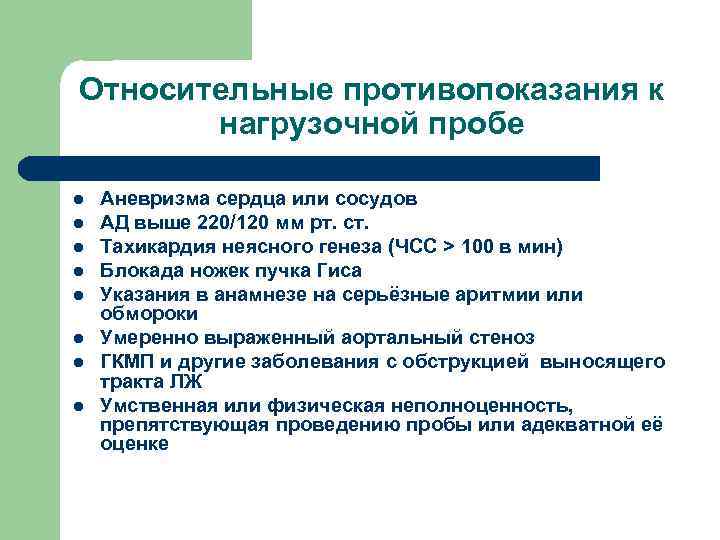

Относительные противопоказания к нагрузочной пробе l l l l Аневризма сердца или сосудов АД выше 220/120 мм рт. ст. Тахикардия неясного генеза (ЧСС > 100 в мин) Блокада ножек пучка Гиса Указания в анамнезе на серьёзные аритмии или обмороки Умеренно выраженный аортальный стеноз ГКМП и другие заболевания с обструкцией выносящего тракта ЛЖ Умственная или физическая неполноценность, препятствующая проведению пробы или адекватной её оценке